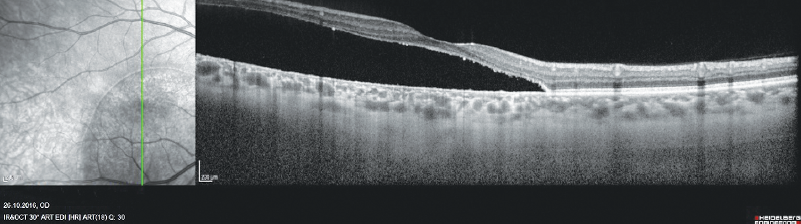

Changes revealed by FA raised the suspicion of an optic disk pit complicated by maculopathy. Repeated OCT, including that in the EDI mode (OCT Spectrais, Heidelberg Engineering, Germany), revealed a high NED in the central area and atrophy of the retinal pigment epithelium. The choroidal thickness in the central area was unchanged; however, an increase in the caliber of large vessels of the choroid and a decrease in the caliber of the choriocapillaris were noted (Fig. 4).

Fig. 4. OCT of patient B. Vertical scan across the foveolar center

Рис. 4. ОКТ пациентки Б. Вертикальный срез через центр фовеолы

In the area of the NED maximum altitude, no increase in the choroidal thickness was revealed also, however, there was a similar change in its structure (Fig. 5).

Fig. 5. OCT of patient B. Horizontal scan across the area of neuroepithelium detachment’s maximal height

Рис. 5. ОКТ пациентки Б. Горизонтальный срез через зону максимальной высоты отслойки нейроэпителия